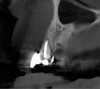

After 3 months of post-orthodontic stabilization, a cone-beam computed tomography scan was taken to re-evaluate the results and plan the future treatment sequence. Tomographic images clearly showed vertical gains in alveolar height, including in the edentulous area corresponding to tooth No. 7 (Figure 10 through Figure 12). The apex of tooth No. 8 was forced-erupted beyond its socket and could be visibly located within the soft tissue.30,33

Fig 11. Tomographic images of teeth Nos. 6 (Fig 10), 7 (Fig 11), and 8 (Fig 12) clearly showed vertical gains in alveolar height, including in the edentulous area corresponding to tooth No. 7. The apex of tooth No. 8 was located within the soft tissue because it was force-erupted beyond its socket.

Figure 11